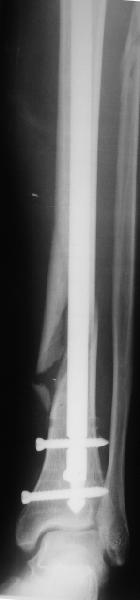

Все наши сомнения связаны с тем, что этих незначительных погрешностей (небольшой вальгус, неглубоко пробит гвоздь, мало запирающих винтов в

дистальном отломке) не одна, а несколько, и вместе они могут значительно осложнить дальнейшую жизнь пациенту. В нашей практике были подобные случаи, при которых после разрешения полной нагрузки либо начинала увеличиваться деформация, либо происходил перелом гвоздя по ближайшему отверстию. Кроме того, при диафизарных переломах, имея в арсенале надежный фиксатор, нет никакой необходимости вынуждать пациента ограничивать нагрузку на ногу в течении 2-3 месяцев.

Взвесив все <<за>> и <<против>>, мы приняли решение и выполнили реостеостинтез: выбили гвоздь до линии перелома, провели отклоняющую

спицу, забили обратно гвоздь и заблокировали внизу 3-мя винтами, вверху одним. Вся операция заняла меньше часа. Сегодня пациент ушел от нас домой с полной нагрузкой на ногу.